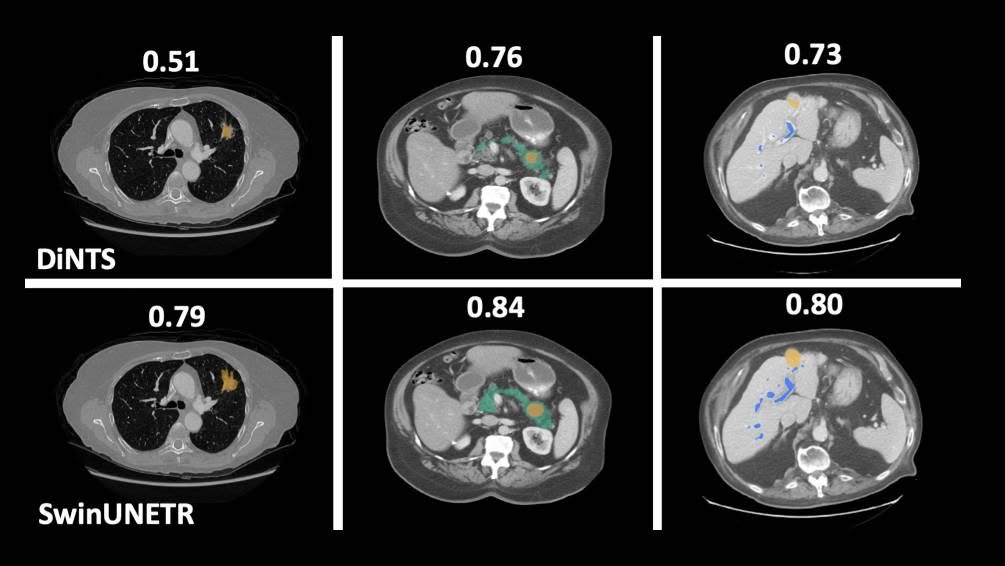

醫療影像分析

有沒有可能未來我們去醫院後,不用等醫師診斷就能知道自己得了什麼病?這就是"AI數位醫療影像分析"。 透過在判讀醫療影像上結合機器學習,便能輔助醫生診斷、預測疾病、評估療效。身為人工智慧的一個分支,透過分析大量的資料,就能學會自己判斷特定疾病,省略人工判斷每一個病例的環節。這次我們將介紹我們訓練的皮膚疾病辨識模型,並調整參數以提高正確率。

演講者:二己 馬詩涵 林筱婷